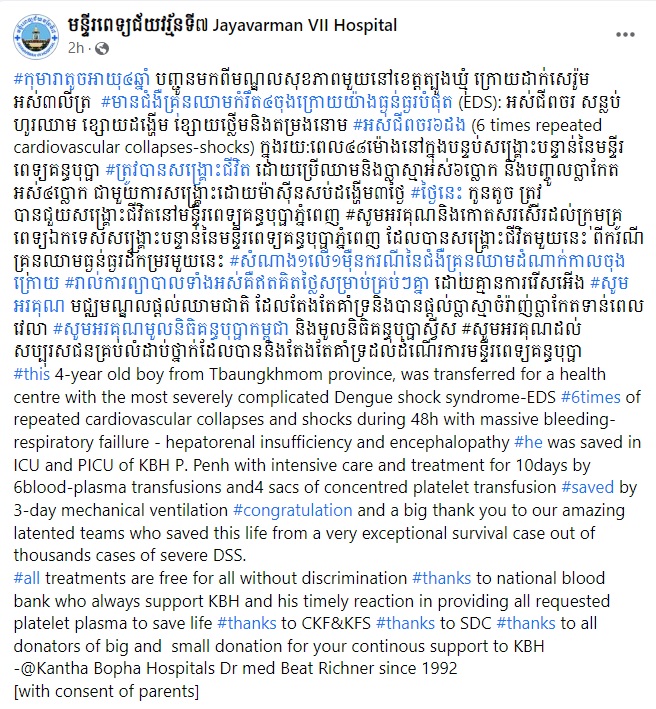

កុមារាតូចអាយុ៤ឆ្នាំរូបនេះ បញ្ជូនមកពីមណ្ឌលសុខភាពមួយនៅខេត្តត្បូងឃ្មុំ ក្រោយដាក់សេរ៉ូមអស់៣លីត្រ។ កុមារានេះមានជំងឺគ្រុនឈាមកម្រិត៤ចុងក្រោយយ៉ាងធ្ងន់ធ្ងរបំផុត (EDS) អស់ជីពចរ សន្លប់ ហូរឈាម ខ្សោយដង្ហើម ខ្សោយថ្លើមនិងតម្រងនោម #អស់ជីពចរ៦ដង (6 times repeated cardiovascular collapses-shocks)។

ក្នុងរយៈពេល៤៨ម៉ោងនៅក្នុងបន្ទប់សង្គ្រោះបន្ទាន់នៃមន្ទីរពេទ្យគន្ធបុប្ផា ត្រូវបានសង្រ្គោះជីវិត ដោយប្រើឈាមនិងប្លាស្មាអស់៦ប្លោក និងបញ្ចូលប្លាកែតអស់៤ប្លោក ជាមួយការសង្រ្គោះដោយម៉ាស៊ីនសប់ដង្ហើម៣ថ្ងៃ ថ្ងៃនេះ កូនតូច ត្រូវបានជួយសង្គ្រោះជីវិតនៅមន្ទីរពេទ្យគន្ធបុប្ផាភ្នំពេញ។

ប្រភពក៏បានអរគុណនិងកោតសរសើរដល់ក្រុមគ្រូពេទ្យឯកទេសសង្គ្រោះបន្ទាន់នៃមន្ទីរពេទ្យគន្ធបុប្ផាភ្នំពេញ ដែលបានសង្គ្រោះជីវិតមួយនេះ ពីករណីគ្រុនឈាមធ្ងន់ធ្ងរដ៏កម្រមួយនេះ។ សំណាង១លើ១ម៉ឺនករណីនៃជំងឺគ្រុនឈាមដំណាក់កាលចុងក្រោយ រាល់ការព្យាបាលទាំងអស់គឺឥតគិតថ្លៃសម្រាប់គ្រប់ៗគ្នា ដោយគ្មានការរើសអើង។ សូមអរគុណ មជ្ឈមណ្ឌលផ្តល់ឈាមជាតិ ដែលតែងតែគាំទ្រនិងបានផ្តល់ប្លាស្មាចំរ៉ាញ់ប្លាកែតទាន់ពេលវេលា សូមអរគុណមូលនិធិគន្ធបុប្ផាកម្ពុជា និងមូលនិធិគន្ធបុប្ផាស្វីស សូមអរគុណដល់សប្បុរសជនគ្រប់លំដាប់ថ្នាក់ដែលបាននិងតែងតែគាំទ្រដល់ដំណើរការមន្ទីរពេទ្យគន្ធបុប្ផា៕